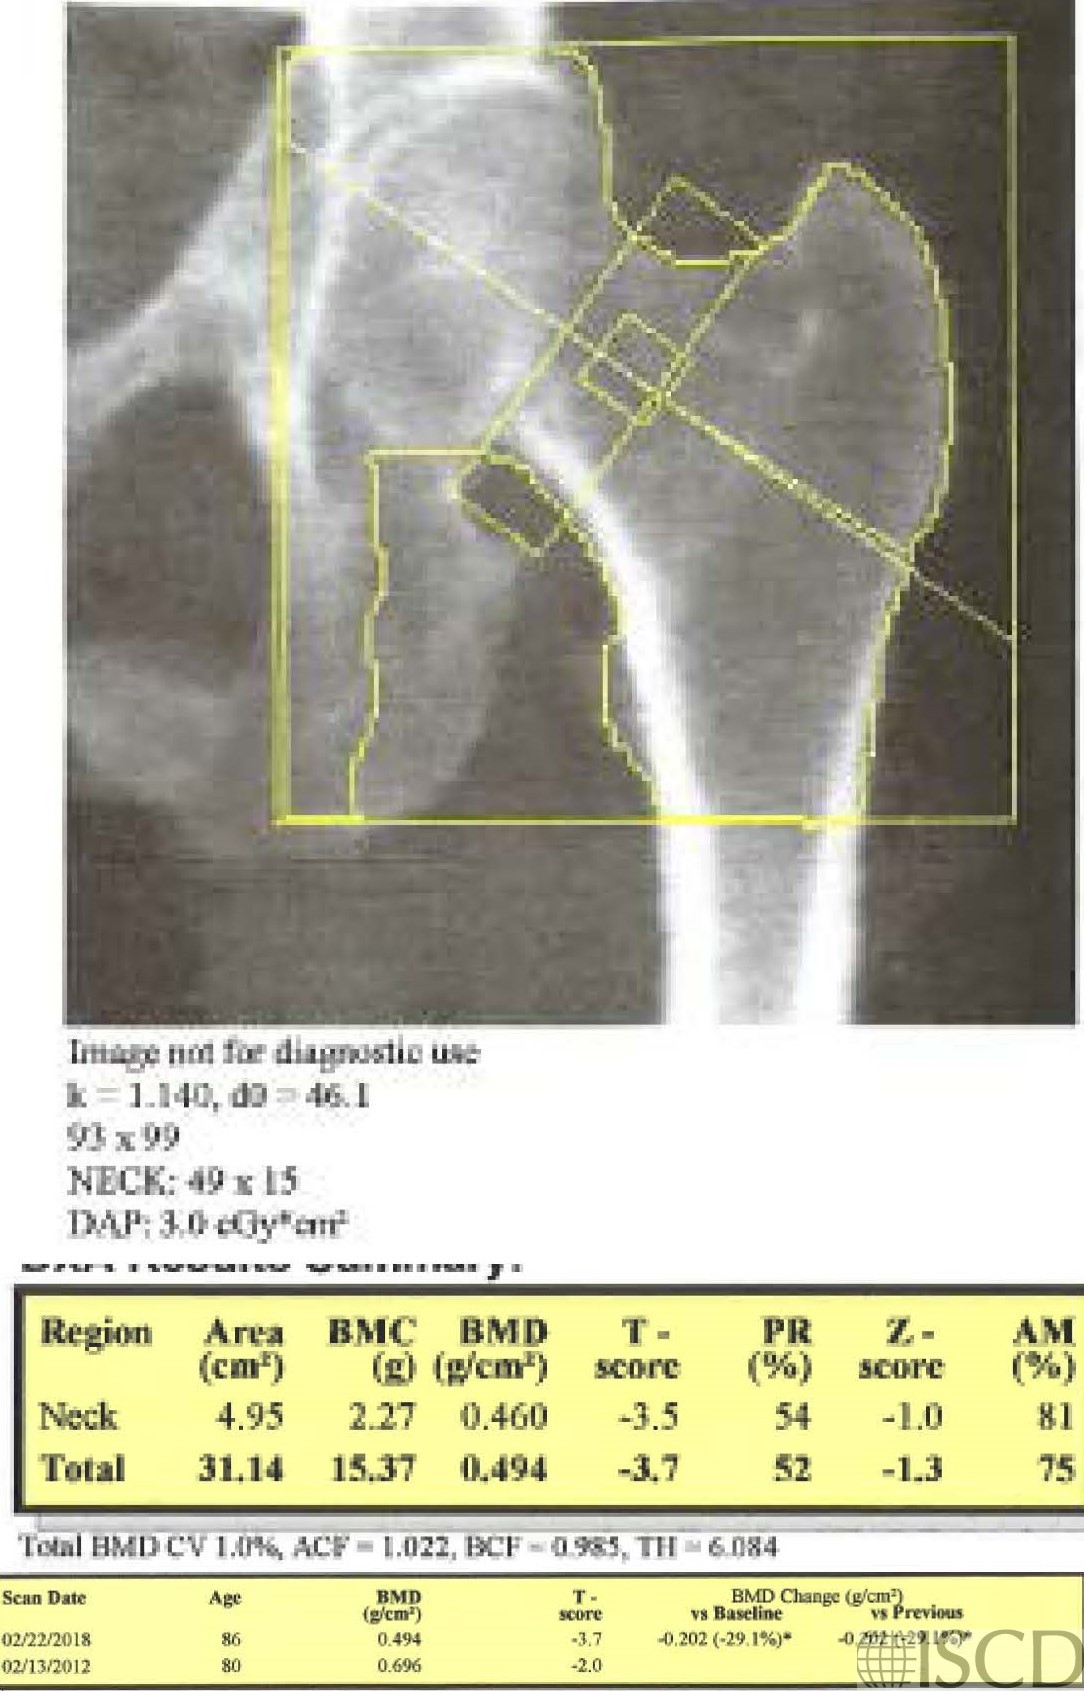

The baseline scan is presented in the upper left panel. In the upper right panel is the follow-up scan. The ischium was omitted differently, and the lesser trochanter was not outlined. The bottom panel shows the corrected scan with the ischium omitted in approximately the same way and the lesser trochanter now outlined. The total hip bone mineral density is higher with the lesser trochanter outlined. The scans were 6 years apart and there is a significant difference at the total hip with both scenarios, however the magnitude of the loss is much greater without the lesser trochanter being outlined.